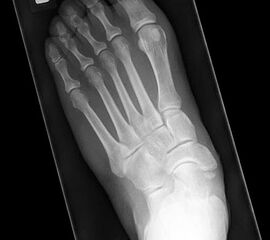

Stehende konventionelle Röntgenbilder eines Fußes mit Planovalgus Deformität Stadium II b dorsoplantar (dp) und seitlich. Auf der dp-Aufnahme zeigt sich die talo-calcaneare Divergenz, der gegenüber dem Kalkaneus nach anterior gleitende Talus und d

Stehende Aufnahmen des Fußes dorsoplantar (dp) und seitlich sowie des OSG anteroposterior (ap) sind die Grundlage der konventionellen Röntgendiagnostik (Abb. 5). Ergänzend werden gelegentlich die Rückfuβ-Alignement Aufnahme nach Saltzman 19 und Vergleichsaufnahmen der Gegenseite durchgeführt.